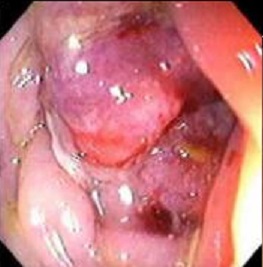

Aspect macroscopique du colonoscopie , sigmoidoscopie

et coloscopie virtuelle d'une adenome carcionoma du colon .

Aspect macroscopique de

coloscopie d'une adenocarcinoma du colon |

Aspect d'une

autre cas de adenome carcinoma du colon . Image

macroscopique d'une sigmoidoscopie |